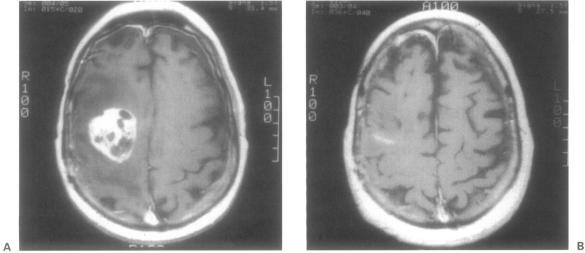

The objective of this article is to evaluate single-fraction or fractionated stereotactic radiotherapy of central nervous system (CNS) and head and neck lesions using intensity-modulated radiotherapy (IMRT) with a commercially available system (Peacocktrade mark, Nomos Corporation, Sewickley, PA). This system allows tomotherapeutic delivery of intensity-modulated radiation, that is, the slice-by-slice treatment of the volume of interest with an intensity-modulated beam, making the delivery of highly conformal radiation to the target possible in both single or multiple fractions mode. During an 18-month period, 43 (21 males and 22 females) patients were treated, using a removable cranial screw-fixation device. Ages ranged from 10 to 77 years (mean, 52.2; median, 53.5). Intra- and extra-axial lesions, including head and neck malignancies and spine metastases, were treated. Clinical target volume ranged from 0.77 to 195 cm(3) (mean, 47.8; median, 29.90). The dose distribution was normalized to the maximum and was prescribed, in most cases, at the 80% or 90% isodose line (range, 65 to 96%; median, 85%; mean, 83.4%) and ranged from 14 to 80 Gy (mean, 48; median, 50). The number of fractions ranged from 1 to 40 (mean, 23; median, 25). In all but one patient, 90% of the prescription isodose line covered 100% of the clinical target volume. The heterogeneity index (the ratio between the maximum radiation dose and the prescribed dose) ranged between 1.0 and 1.50, whereas the conformity index (the ratio between the volume encompassed by the prescription isodose line and the clinical target volume) ranged between 1.0 and 4.5. There were no complications related to the radiation treatment. With a median follow-up of 6 months, more than 70% of our patients showed decreased lesion size. Stereotactic IMRT of CNS and head and neck lesions can be delivered safely and accurately. The Peacock system delivers stereotactic radiation in single or multiple fractions and has no volume limitations. It has been used to treat intracranial, head and neck, and spinal lesions. The option of fractionation, the lack of volume constraint, and the capability of treating intracranial, head and neck, and spinal pathology make stereotactic IMRT a valuable adjunct to established stereotactic radiotherapy systems delivering convergent-beam irradiation using the Linac or Gamma Knife. In a clinical setting that offers Linac, Gamma Knife radiosurgery, and conformal stereotactic radiotherapy, the latter may have advantages for treating large (> 25-cm(3)) and irregular lesions, especially when fractionation is considered useful.